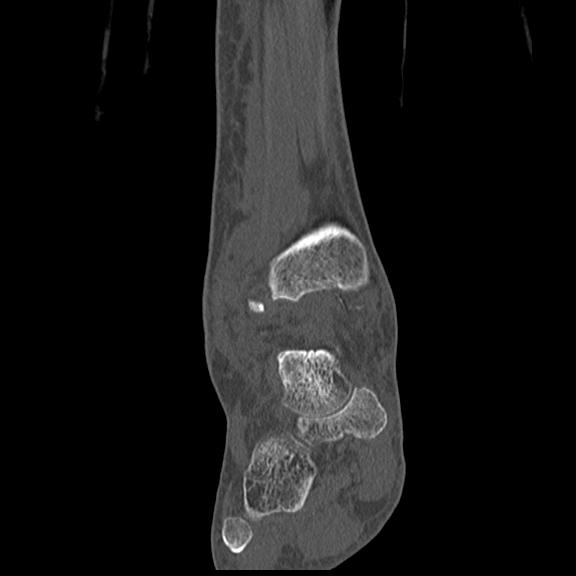

102755 1/4 2R 1/15 2R 右足関節 68歳女性 右三果脱臼骨折